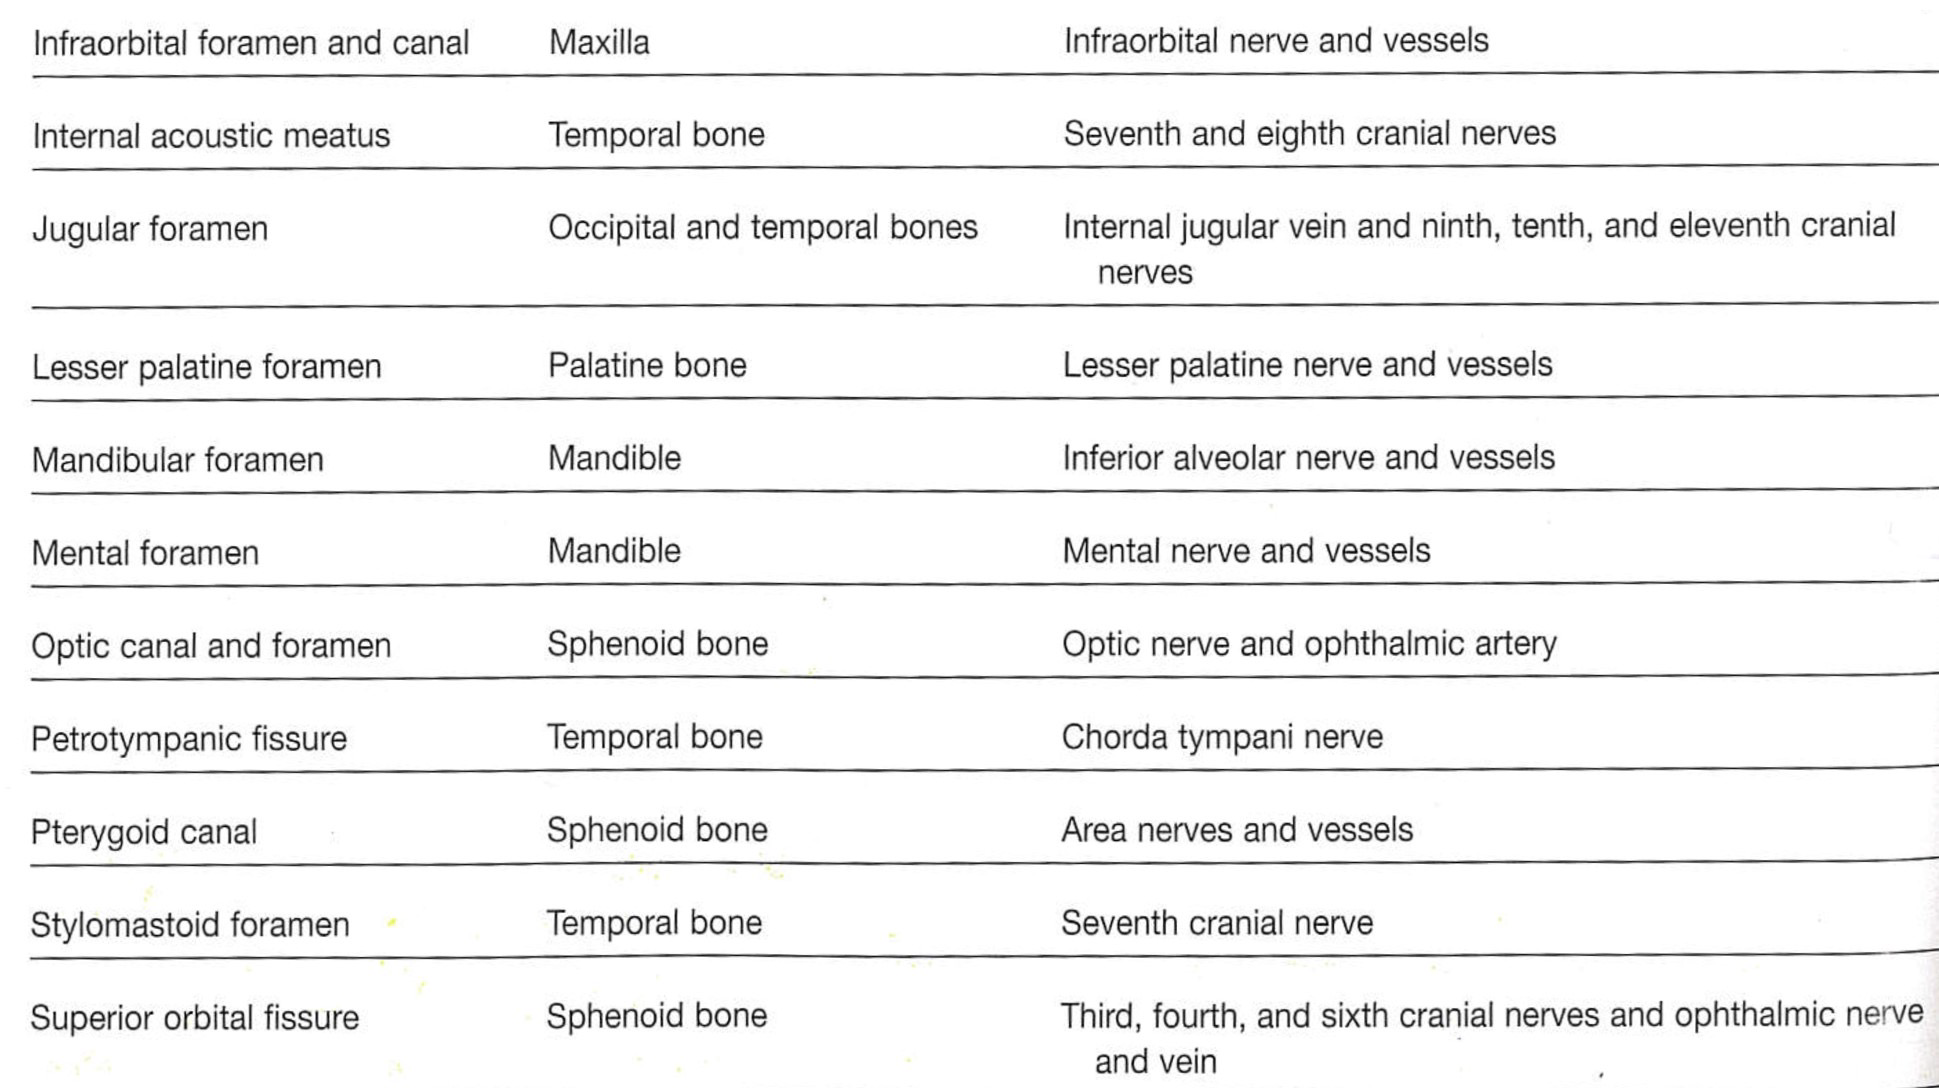

| CN | Origin | foramen |

|---|---|---|

| I | 嗅球 | cribriform plate |

| II | Optic Chiasma | optic canal |

| III, IV | Midbrain | sup orbital fissure |

| V1, VI | pons | |

| V2 | foramen rotundum | |

| V3 | foramen ovale | |

| VII | Internal coustic meatus | |

| VIII | Pons, Medulla 之間 | |

| IX, X, XI | Medulla | jugular foramen |

| XII | Hypoglossal canal |

Foramen rotundum

Foramen ovale

Foramen spinosum

Pterygoid canal

Foramen lacerum (破裂孔)

Optic canal

Sup. orbital fissure

- Carotid canal

- Ext. acoustic meatus

- Int. acoustic meatus

- Jugular foramen

- Stylomastoid foramen

- Petrotympanic fissure

- Hypoglossal canal

- Foramen magnum

- Jugular foramen